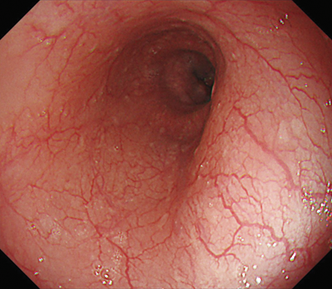

EVIS LUCERA ELITE × GIF1200N 症例画像

遠景部分において明るい視野が確保できる(病変の例)